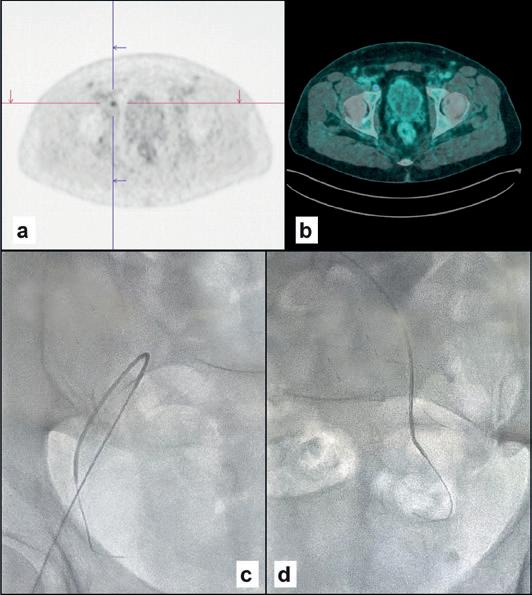

CASE ONE

Male, 76 years old

Spiculated lung nodule, 14mm (A) in the right lower lobe, ischaemic heart disease, respiratory failure. Liquid biopsy from the right subclavian vein (B, C) with a finding of pathogenic mutation CDH1. Surgical histological confirmation of minimally invasive adenocarcinoma.

this biomarker. The simplest method, investigated by us and confirmed by another research group, is to draw venous blood in proximity to the tumour site. Percutaneous venous catheterisation is part of the armamentarium of interventional radiologists and relies on their familiarity with navigating the vascular system under fluoroscopic guidance. Sampling sites can be chosen as dictated by the natural history of the disease, which includes both primary and metastatic sites.

FOUR

Male, 63 years old

Operated prostate adenocarcinoma, Gleason grade 7 (3+4), PSA increase to 0.26 six years after surgery. PET PSMA (A, B) positive for right pelvic adenopathy. In the right hypogastric vein (C) we found ESR1, FGFR2 and MAP2K1 mutations. In the left (D) vein, mutations were FGFR2, MAP2K1 and RET. Pelvic radiotherapy is indicated.

CASE